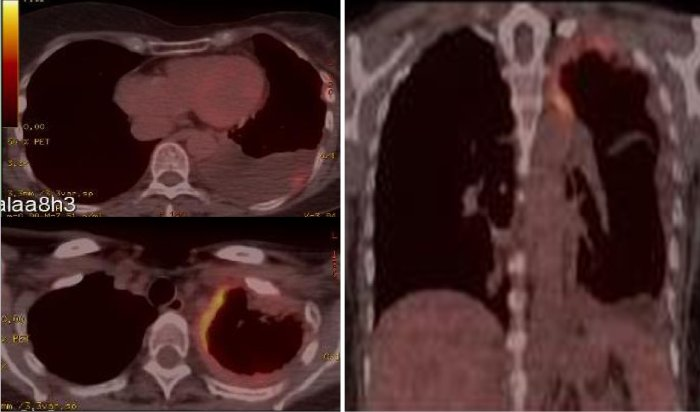

Relato de caso mesotelioma maligno de pleura com associação. Lioma maligno de pleura. Diagnóstico definitivo realizado com fragmentos provenientes da peça cirúrgica por meio de microscopia eletrônica que mostrou presença de microvilosidades características de células neoplásicas mesoteliais. Diagnóstico definitivo mesotelioma maligno de pleura do tipo epitelial. ¿cuáles son los factores de riesgo para el mesotelioma. El mesotelioma peritoneal, que se forma en el abdomen, puede resultar de toser y tragar las fibras de asbesto inhaladas. Muchas personas están expuestas a niveles muy bajos de amianto natural en el aire exterior en polvo que proviene de rocas y suelos que contienen amianto. Cáncer de pulmón wikipedia, la enciclopedia libre. El cáncer de pulmón es un conjunto de enfermedades resultantes del crecimiento maligno de células del tracto respiratorio, en particular del tejido pulmonar, y uno de los tipos de cáncer más frecuentes a nivel mundial. [1] el cáncer de pulmón suele originarse a partir de células epiteliales, y puede derivar en metástasis e infiltración a otros tejidos del cuerpo. Mesotelioma maligno national cancer institute. El mesotelioma maligno es un cáncer de la capa delgada de tejido (mesotelio) que reviste los pulmones, la pared del tórax y el abdomen. La exposición al amianto (asbesto) es uno de los factores principales de riesgo de mesotelioma. Para obtener más información sobre el tratamiento del. Mesotelioma pleural maligno gaceta mexicana de oncología. El mesotelioma pleural maligno es una neoplasia con gran mortalidad de 99% a 5 años, con pocas expectativas de tratamiento, enfrentándose a diferentes problemas como son la rareza del padecimiento, la dificultad para estadificarla, la naturaleza agresiva, poca sensibilidad a quimioterapia. Cáncer comunidad de madrid. El cáncer no es una enfermedad, sino más bien muchas enfermedades. De hecho, hay unos cien tipos diferentes de cáncer o tumores. Todos los cánceres empiezan en las células. Las células son las unidades básicas que forman los tejidos del cuerpo. Para entender mejor qué es el cáncer, es necesario saber cómo las células normales se vuelven cancerosas. Mesotelioma maligno do peritoneu researchgate. O mesotelioma maligno do peritoneu é um tumor raro (12 casos em cada milhão de habitantes por ano) (1), sendo que o atingimento peritoneal isolado se limita a 1020% dos casos (2). A sua. Medicinanet. A; a00 cólera; a01 febres tifóide e paratifóide; a02 outras infecções por salmonella; a03 shiguelose; a04 outras infecções intestinais bacterianas.